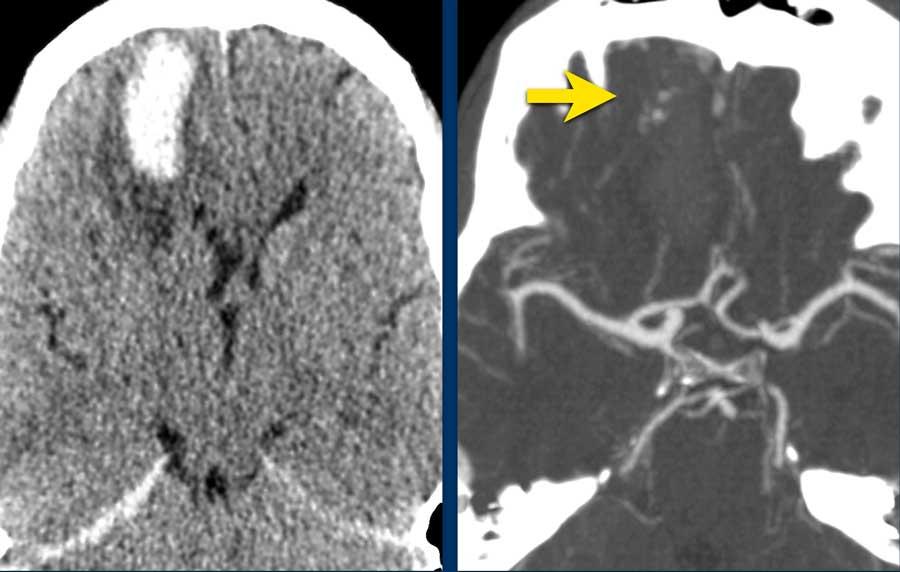

Bệnh nhân này được nhập vào đơn vị đột quỵ với chẩn đoán nhồi máu não mới trong vùng phân bố của động mạch não giữa trái.

Do đến viện muộn, ngoài cửa sổ điều trị tiêu huyết khối, bệnh nhân không được chỉ định liệu pháp này.

CT không tiêm thuốc cản quang (NECT) tái khám (hình A) được chỉ định do tình trạng lâm sàng xấu đi, cho thấy vùng giảm tỷ trọng giới hạn rõ trong vùng phân bố của động mạch não giữa trái. Trong vùng giảm tỷ trọng này, ghi nhận các ổ tăng tỷ trọng nhỏ, mờ nhạt.

MRI thực hiện vài giờ sau trong cùng ngày cho thấy các ổ xuất huyết (mũi tên) phù hợp với hình ảnh chuyển dạng xuất huyết dạng chấm xuất huyết (petechial) của ổ nhồi máu thiếu máu cục bộ.